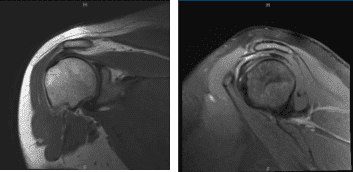

The patient presented MRI results of left shoulders that showed Moderate grade partial-thickness bursal surface tear of the distal supraspinatus tendon with accompanying subacromial subdeltoid bursitis.

MRI-3T Left Shoulder non-contrast